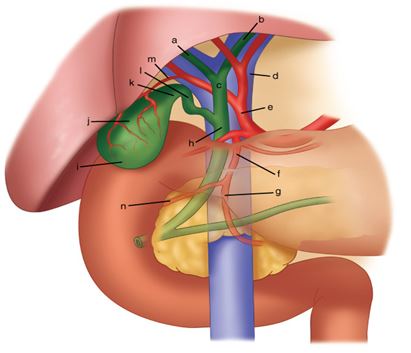

قیمت: 96٬000 تومان - دسته بندی فایل: پاورپوینتپاورپوینت اختلالات روده و رکتوم

فروش ویژه فایل های پاورپوینت حرفه ای اختلالات روده و رکتوم با تخفیف استثنایی فقط 123000 هزار تومان تعداد اسلاید : 102 اسلاید